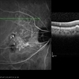

- A 51-year-old female presented with a left pigmented choroidal lesion, involving the supero-temporal macula (A). Fundus autofluorescence (B) showed mottling and focal areas of hiperautofluorescence and the structural optical coherence tomography (OCT) (C) was compatible with choroidal nevus, with choriocapillaris compression and choroidal shadowing. In the nasal aspect of the nevus, there was sharp-peaked pigmented epithelium detachment (PED) with associated subretinal fluid, suspicious of a polypoidal lesion. Complementary testing with OCT-angiography (D) confirmed the vascularized nature of the sharp PED. Fluorescein angiography (E) showed masking from the pigmented choroidal lesion with hyperfluorescence from the PEDs and indocyanine green angiography (F) revealed two “hot spots” confirming the presence of choroidal polyps. Polypoidal choroidal vasculopathy complicating benign choroidal nevus is an unusual presentation but should be excluded and differentiated from malignant transformation.